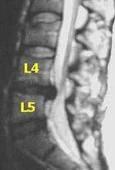

Tratamiento Endoscopico de las Hernias Discales

@saludymedicina